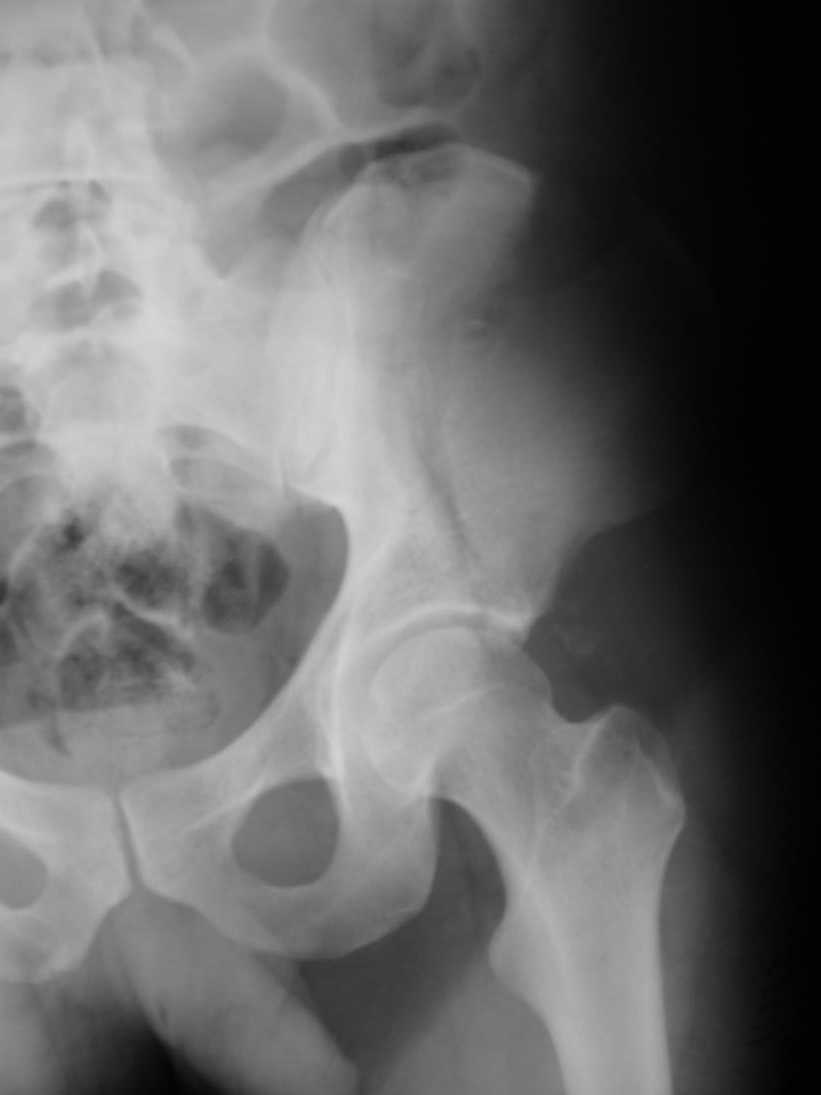

Поступил пациент после кататравмы (упал с высоты 4м). После обследования установлен Ds: Сочетанная травма. ЗТГК перелом 5-6 ребер справа. Ушиб левого леогкого. Оскольчатый перелом крыла подвздошной кости слева, со смещением. в экстренном порядке выполнена операция о/синтез таза стержневым аппаратом. Снимки прилагаются. Пациент со 2-го дня стал ходить без костылей. Из анамнеза жизни у пациента имеется гепатит В и С, с 1998г. употребляет наркотики (героин 1г в день нормальная доза). На контрольных снимках таза в аппарате смещение отломков сохраняется, да еще и стержни сломались. Подскажите ув.коллеги, как поступить в данной ситуации: оставить все как есть или добиваться репозиции в аппарате, или планировать на открытую репозицию. На сегодняшний день пациент стабилен, по анализам компенсирован. Принимает героин по другому справиться не может. С ув. Андрей

А сколько времени прошло после травмы? Аппарат лучше убрать: в таком виде он не выполняет никаких функций, а сломанные стержни скорее всего воспалятся и помешают доступу, если решите оперировать открыто. Целесообразно, как мне кажется сделать проекции Judet, чтоб определиться с линией перелома и возможным вовлечением вертлужной впадины. Вообще же лечение переломов крыла аппаратом - дело достаточно утомительное и часто неблагодарное - сложно управлять ротационным смещением и отведением/приведением фрагментов крыла, можно ухудшить стояние отломков.

Уважаемый Андрей, у пациента имеется перелом передней колонны,и после наложения аппарата положение отломков ухудшилось. возможно не из-за ваших действий а за счет тяги четырехглавой мышцы. Обе ости настойчиво будут тянуть крыло вниз.

вариант 1 в свежем случае репозиция и трансфрактурная фиксация через проколы под ЭОПом (сгибание бедра облегчит репозицию)

Вариант 2 нет винтов - закрытая репозиция, фиксация аппаратом но на стороне повреждения вместо стержней 5-10 трансфрактурных спиц введенных через гребень

Вариант 3 Нет Эопа, срок больше 10 дней - подвздошный доступ, репозиция щипцами (можно крокодилами за винты) фиксация двумя пластинами по внутренней стороне на разных уровнях + винты прансфрактурно. (если больной очень активный для нейтрализации мышц живота можно небольшой аппаратик набросить сверху).